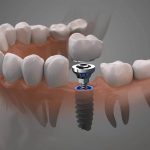

Dental Implant Surgeons Near Me

During your initial examination,At dental implants dentures, our dental implant surgeons will examine your existing teeth, amount of bone mass in your jaw, and the overall health of your gums. Schedule a consultation today with our trusted specialists!